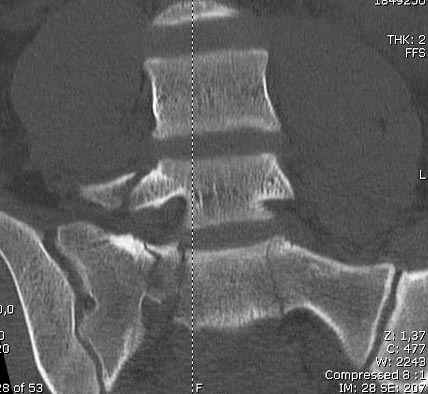

Здесь слайды случая больного с политравмой, включающей сегментарный перелом бедра и повреждение таза с нарушением тазового кольца, разрыв симфиза и перелома крестца зон 2 и 3.

На множественных слайдах важные моменты операции. Хотел бы подчеркнуть, как важно иметь возможности всех необходимых ренгенограмм, включая компютерную томографию и стандартных внутритазовых рентгенограмм (инлет и оутлет).